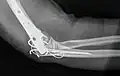

Bei Erwachsenen bedeuten perkondyläre Frakturen, dass die Trochlea humeri mit den Epikondylen nicht nur vom Schaft getrennt, sondern auch in sich, in zwei oder mehr Teile, gebrochen ist. Die operative Versorgung ist aufwändig: Der Nervus ulnaris muss freigelegt, das Olecranon durchsägt und mit dem Musculus triceps brachii hochgeklappt werden. Wie ein dreidimensionales Puzzle wird die Kondylenrolle rekonstruiert und mit Kirschner-Drähten und Kleinfragment-Lochschrauben zusammengehalten. Mit Drittelrohr- oder Rekonstruktionsplatten an beiden Seiten wird die (übungsstabile) Verbindung zum Schaft wiederhergestellt. Gut geeignet, aber teuer sind anatomisch vorgeformte winkelstabile Platten (Mayo). Das Olecranon wird mit einer Zuggurtung refixiert. In Hinblick auf die komplexe Anatomie des unteren Humerusendes sollte man sich bei der Rekonstruktion ein Humerusmodell zur Seite legen.